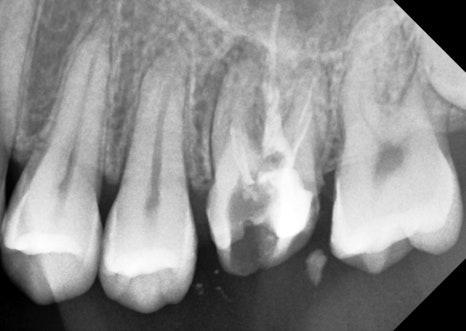

엑스레이를 찍어보니

뿌리에 염증이 잡혀있었어요.

재신경치료 전/후 비교

엑스레이를 볼 줄 모르더라도

왼쪽은 지저분하고

오른쪽은 깔끔해보이시죠?

맞습니다. 깔끔하게 잘 됐습니다.

하얗게 문어다리처럼 뻗어있는 것들이

신경관에 채운 약재인데요

깨끗하게 잘 들어가서

재신경치료가 잘 마무리 됐습니다.

이전 원장님께서 못찾으셨던 신경관도 찾아서

잘 마무리했어요.